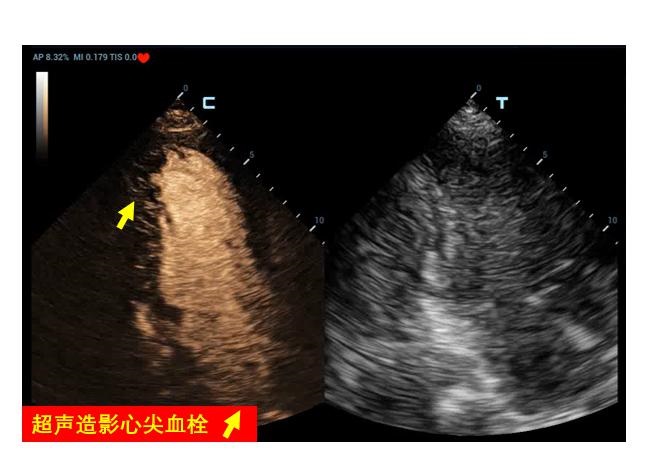

5 特殊超声检查和技术 5.1 超声造影超声造影常用于创伤出血患者的脏器破裂、出血部位查找,也常用于心腔内膜的清晰显示。虽然目前在ECMO患者中使用超声造影剂的安全性没有足够证据支持,但已有少量病例报道应用超声造影协助发生南北综合征的VA-ECMO患者寻找血流接触平面位置、判断主动脉瓣反流、协助明确左心室血栓形成(图 29)及撤机后使用超声造影协助评估穿刺点部位血管并发症等多方面应用[25-28]。

| 图 29 左心尖血栓形成 |